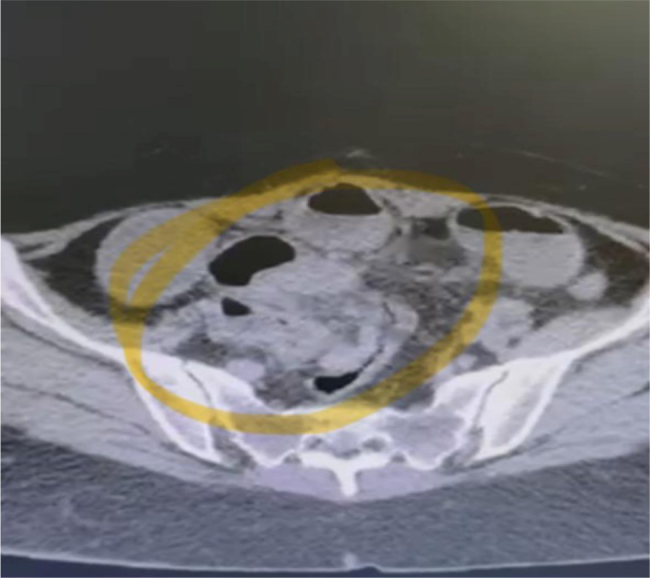

Endometriosis is a chronic inflammatory condition affecting 5-10% of women of reproductive age, most commonly involving pelvic organs. Gastrointestinal endometriosis, particularly at the terminal ileum, is rare and can clinically mimic other conditions such as Crohn's disease, posing significant diagnostic challenges. We report the case of a 45-year-old woman with no prior medical or gynecologic history who presented with a 1-week history of nausea, vomiting, abdominal pain, and obstipation. Imaging studies revealed terminal ileal lesions, and colonoscopy identified a large obstructive polypoid lesion 4 cm proximal to the ileocecal valve. She underwent laparoscopic ileocolic resection, which revealed an obstructed and perforated terminal ileum. Histopathological analysis demonstrated florid granulation tissue, subserosal fibrosis, and a purulent exudate, with endometriotic inclusions comprising endometrial glands and stroma in the terminal ileum and appendix. The ileal and colonic mucosa were unremarkable, and no reactive lymphadenopathy was found. A final diagnosis of ileal endometriosis was made. Postoperatively, the patient recovered well, required no additional medical therapy, and experienced a significant improvement in symptoms without recurrence. This case highlights an unusual presentation of terminal ileal endometriosis causing small bowel obstruction and perforation, masquerading as Crohn's disease. The absence of typical gynecologic symptoms or mucosal abnormalities underscores the diagnostic complexity. Recognition of this rare entity is crucial, as timely surgical intervention can be curative and significantly enhance patient outcomes. This case reinforces the importance of maintaining a broad differential diagnosis in women presenting with unexplained gastrointestinal symptoms and ileal lesions.

Learning points: This case underscores the rare and deceptive presentation of ileal endometriosis mimicking Crohn's disease, culminating in small bowel obstruction and perforation in a patient without any prior history or gynecologic symptoms.What sets this case apart is the presence of both ileal and appendiceal endometriotic inclusions, in the absence of typical mucosal involvement or prior diagnosis of endometriosis.The diagnosis was only confirmed postoperatively through histopathology, reinforcing the importance of considering endometriosis in the differential diagnosis of terminal ileal lesions-even in patients beyond peak reproductive years and with no classic symptoms.